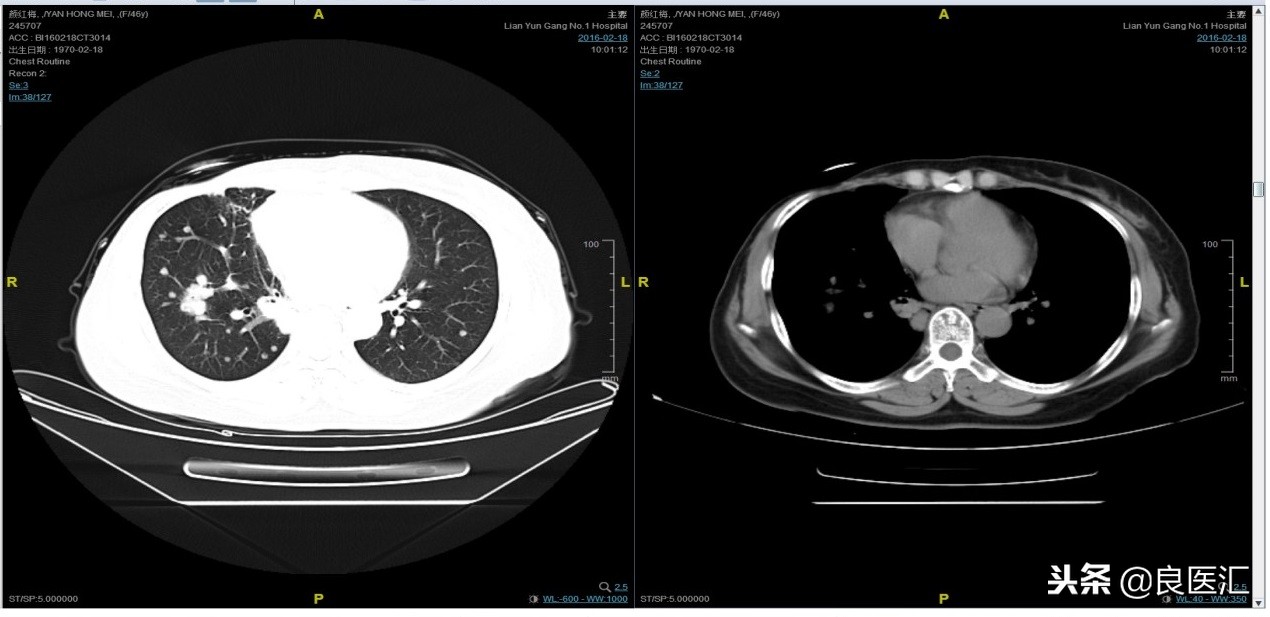

随访至2016-2-18,肺部病灶进展,肺内转移病灶增多。PFS2=10个月。

三线解救治疗及评价

从2016-2-19开始给予紫杉醇+曲妥珠单抗治疗,紫杉醇240mg,3周重复,曲妥珠单抗330mg三周重复。患者末次应用曲妥珠单抗和紫杉醇时间为2016-6-24,紫杉醇共应用4周期。